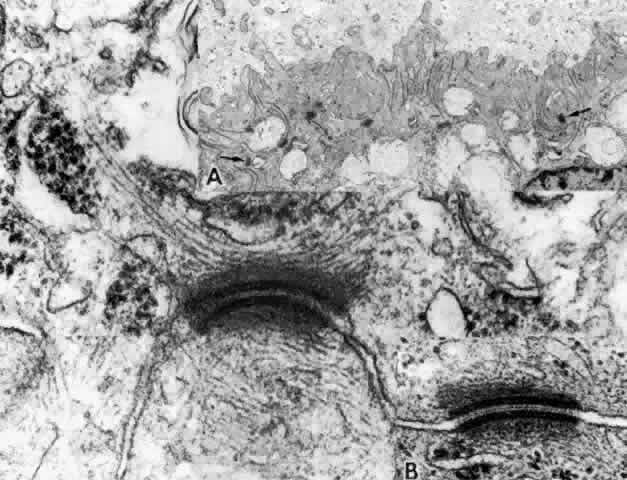

Fig. 16. Ciliary epithelium in the anterior pars plicata of a 19-year-old. Posterior

chamber surface (PC) of the nonpigmented epithelium (NPE) has a sawtooth

pattern seen irregularly throughout this layer with aging. Mitochondria (m) are

large, plentiful, and show artifactual hydropic change. Rough

endoplasmic reticulum is present below the nuclei (asterisk). Note

that the apices of the pigmented epithelial cells (PE) are conical, with

prolongations of NPE between them. (X 8320) Fig. 16. Ciliary epithelium in the anterior pars plicata of a 19-year-old. Posterior

chamber surface (PC) of the nonpigmented epithelium (NPE) has a sawtooth

pattern seen irregularly throughout this layer with aging. Mitochondria (m) are

large, plentiful, and show artifactual hydropic change. Rough

endoplasmic reticulum is present below the nuclei (asterisk). Note

that the apices of the pigmented epithelial cells (PE) are conical, with

prolongations of NPE between them. (X 8320)